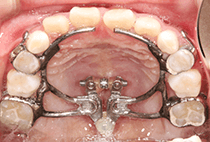

20代女性の患者さま。

八重歯の見た目が気になってご来院されましたが、実は顎の痛みや開口障害など、顎関節症の症状もありました。

そのため、かみ合わせと顎関節症の治療を同時に行ったにもかかわらず、2年間で治療が終了。

かみ合わせが整い咬筋の過緊張も改善しました。咬筋の肥大も治ってフェイスラインがすっきりしました。

最終的には美しい歯並びと、安定した痛みのないかみ合わせが実現しました。

八重歯が気になる

叢生、顎関節症、開口障害

20代女性

矯正治療2年

24回

唇側矯正

矯正:1,161,600円+毎月調整量:6,050円

しっかり前歯を下げるために、インプラントアンカーを使用してコントロールしました。

かみ合わせが整うと咬筋の過緊張が改善。

過緊張による筋肉肥大も改善しフェイスラインもすっきりしました。